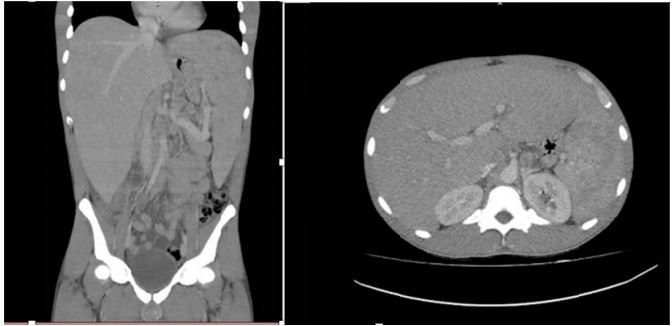

Mulher, 23 anos, procura atendimento referindo febre diária, astenia e perda de 8kg em um mês, além de aumento do volume abdominal com empachamento pós-prandial. Exame físico: Regular estado geral, emagrecida descorada (+2/4); micropoliadenopatia cervical bilateral. Abdômen: fígado palpável a 8cm do RCD, baço a 8cm RCE, doloroso à palpação. Exames laboratoriais: hemoglobina 8,7g/dL; leucócitos 43.320/mm³ (60% eosinófilos), plaquetas 98.00/mm³. Tomografia computadorizada de abdômen: imagem abaixo.

Realizada punção esplênica: presença de estruturas com parede dupla birrefringente e brotamentos.